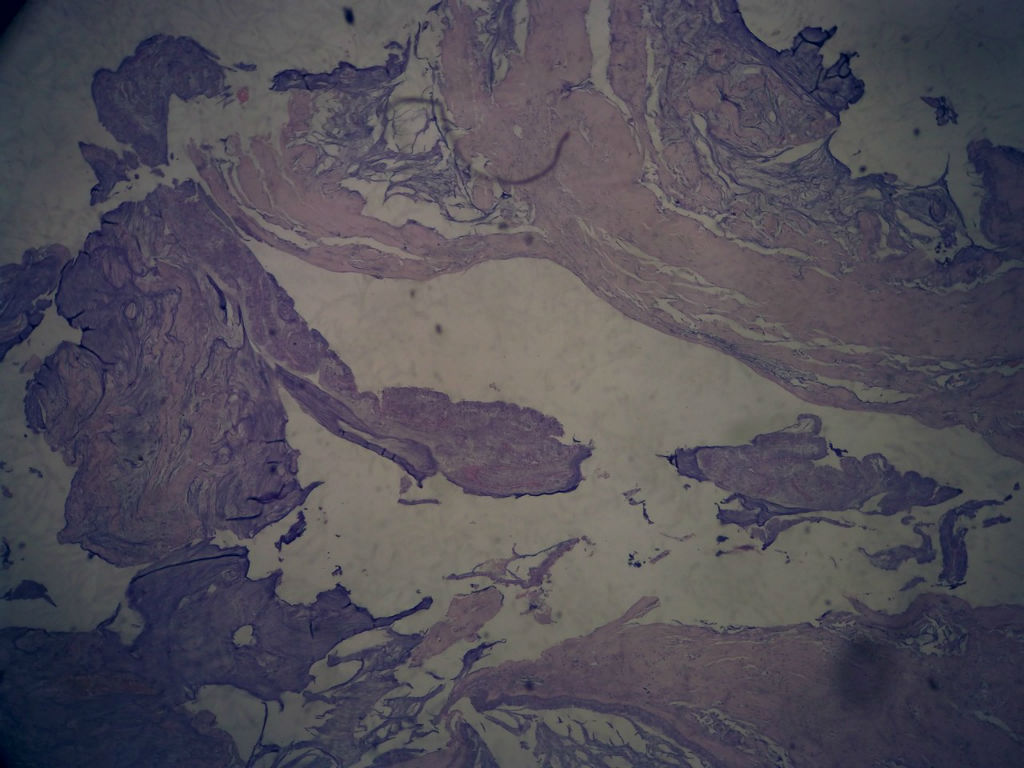

女,80岁,阑尾区肿块。

送检为不规则组织多块,粘滑,解剖结构辨认不清。术中探查双侧卵巢无异常。

• 女,80岁,阑尾区肿块。图1

图1

阑尾粘液性肿瘤,癌的可能性大

粘液长在肌层,而且漂浮着可疑上皮细胞,最大可能粘液腺癌。